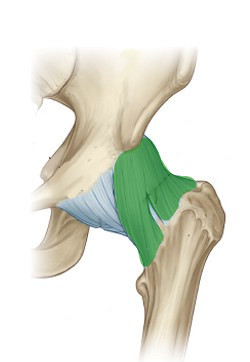

What is this structure?

Ischiofemoral ligament of hip

What is this structure?

Ileofemoral ligament of hip

What is this structure?

Pubofemoral ligament of hip